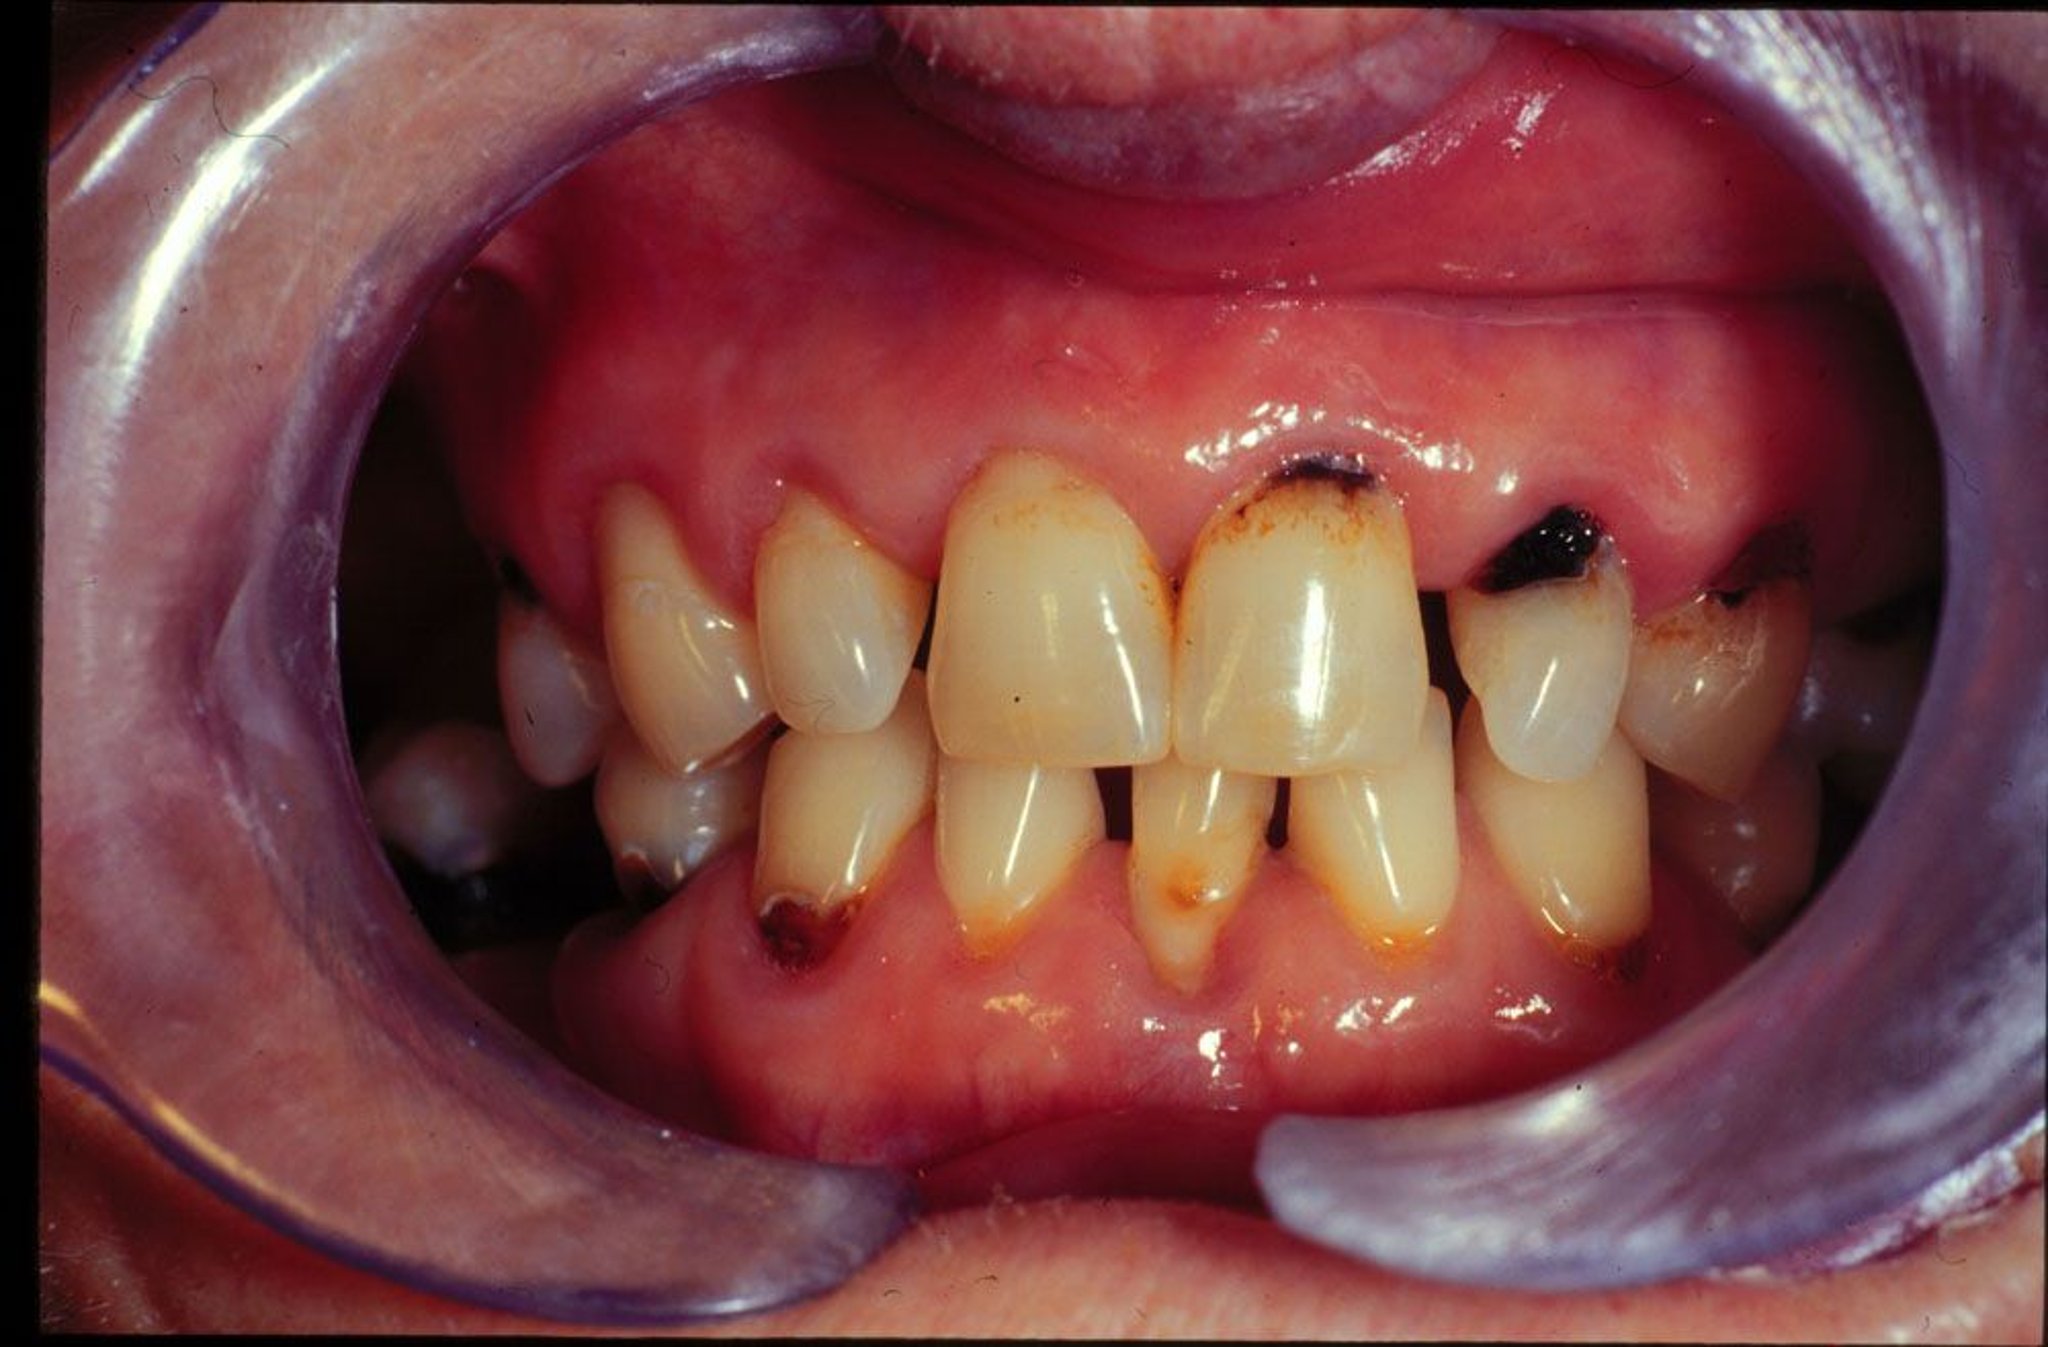

Cos’è la carie?

La carie danneggia parti dei denti.

• I batteri si accumulano sullo smalto dei denti e producono acidi che forano il dente; questi fori sono chiamati carie

• Quando la carie aumenta di dimensioni e attraversa lo smalto arrivando all’interno del dente, provoca dolore ai denti

I batteri, la saliva e residui di cibo formano un sottile strato chiamato placca che aderisce al dente. La placca si indurisce nel tempo e si trasforma in tartaro. Il tartaro di solito è giallo ed è talvolta visibile alla base dei denti. I batteri che vivono nella placca e nel tartaro sono difficili da eliminare.

• Gengive ritirate alla base dei denti (recessione gengivale)